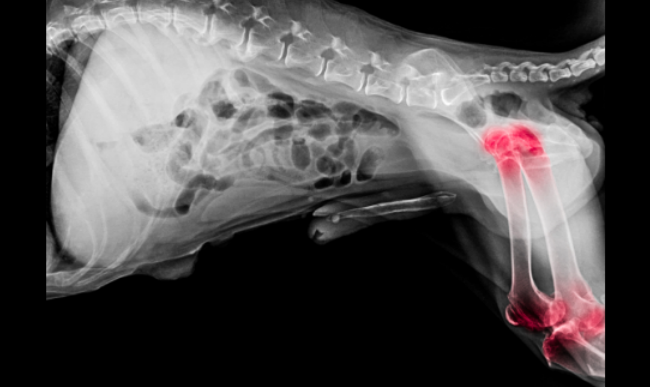

X-ray of a dog’s hind leg showing hip and knee joints highlighted in red, suggesting hip dysplasia

The examination of hip laxity will be achieved by starting with a physical examination and special maneuvers (such as the Ortolani test) by your vet. If they suspect dysplasia, they'll usually recommend X-rays, often under sedation so the dog relaxes and the images are accurate.

Radiographs can show joint subluxation, remodeling, and the level of degenerative change. Organizations like OFA also provide screening protocols and certification for breeders/owners who want hip uations.